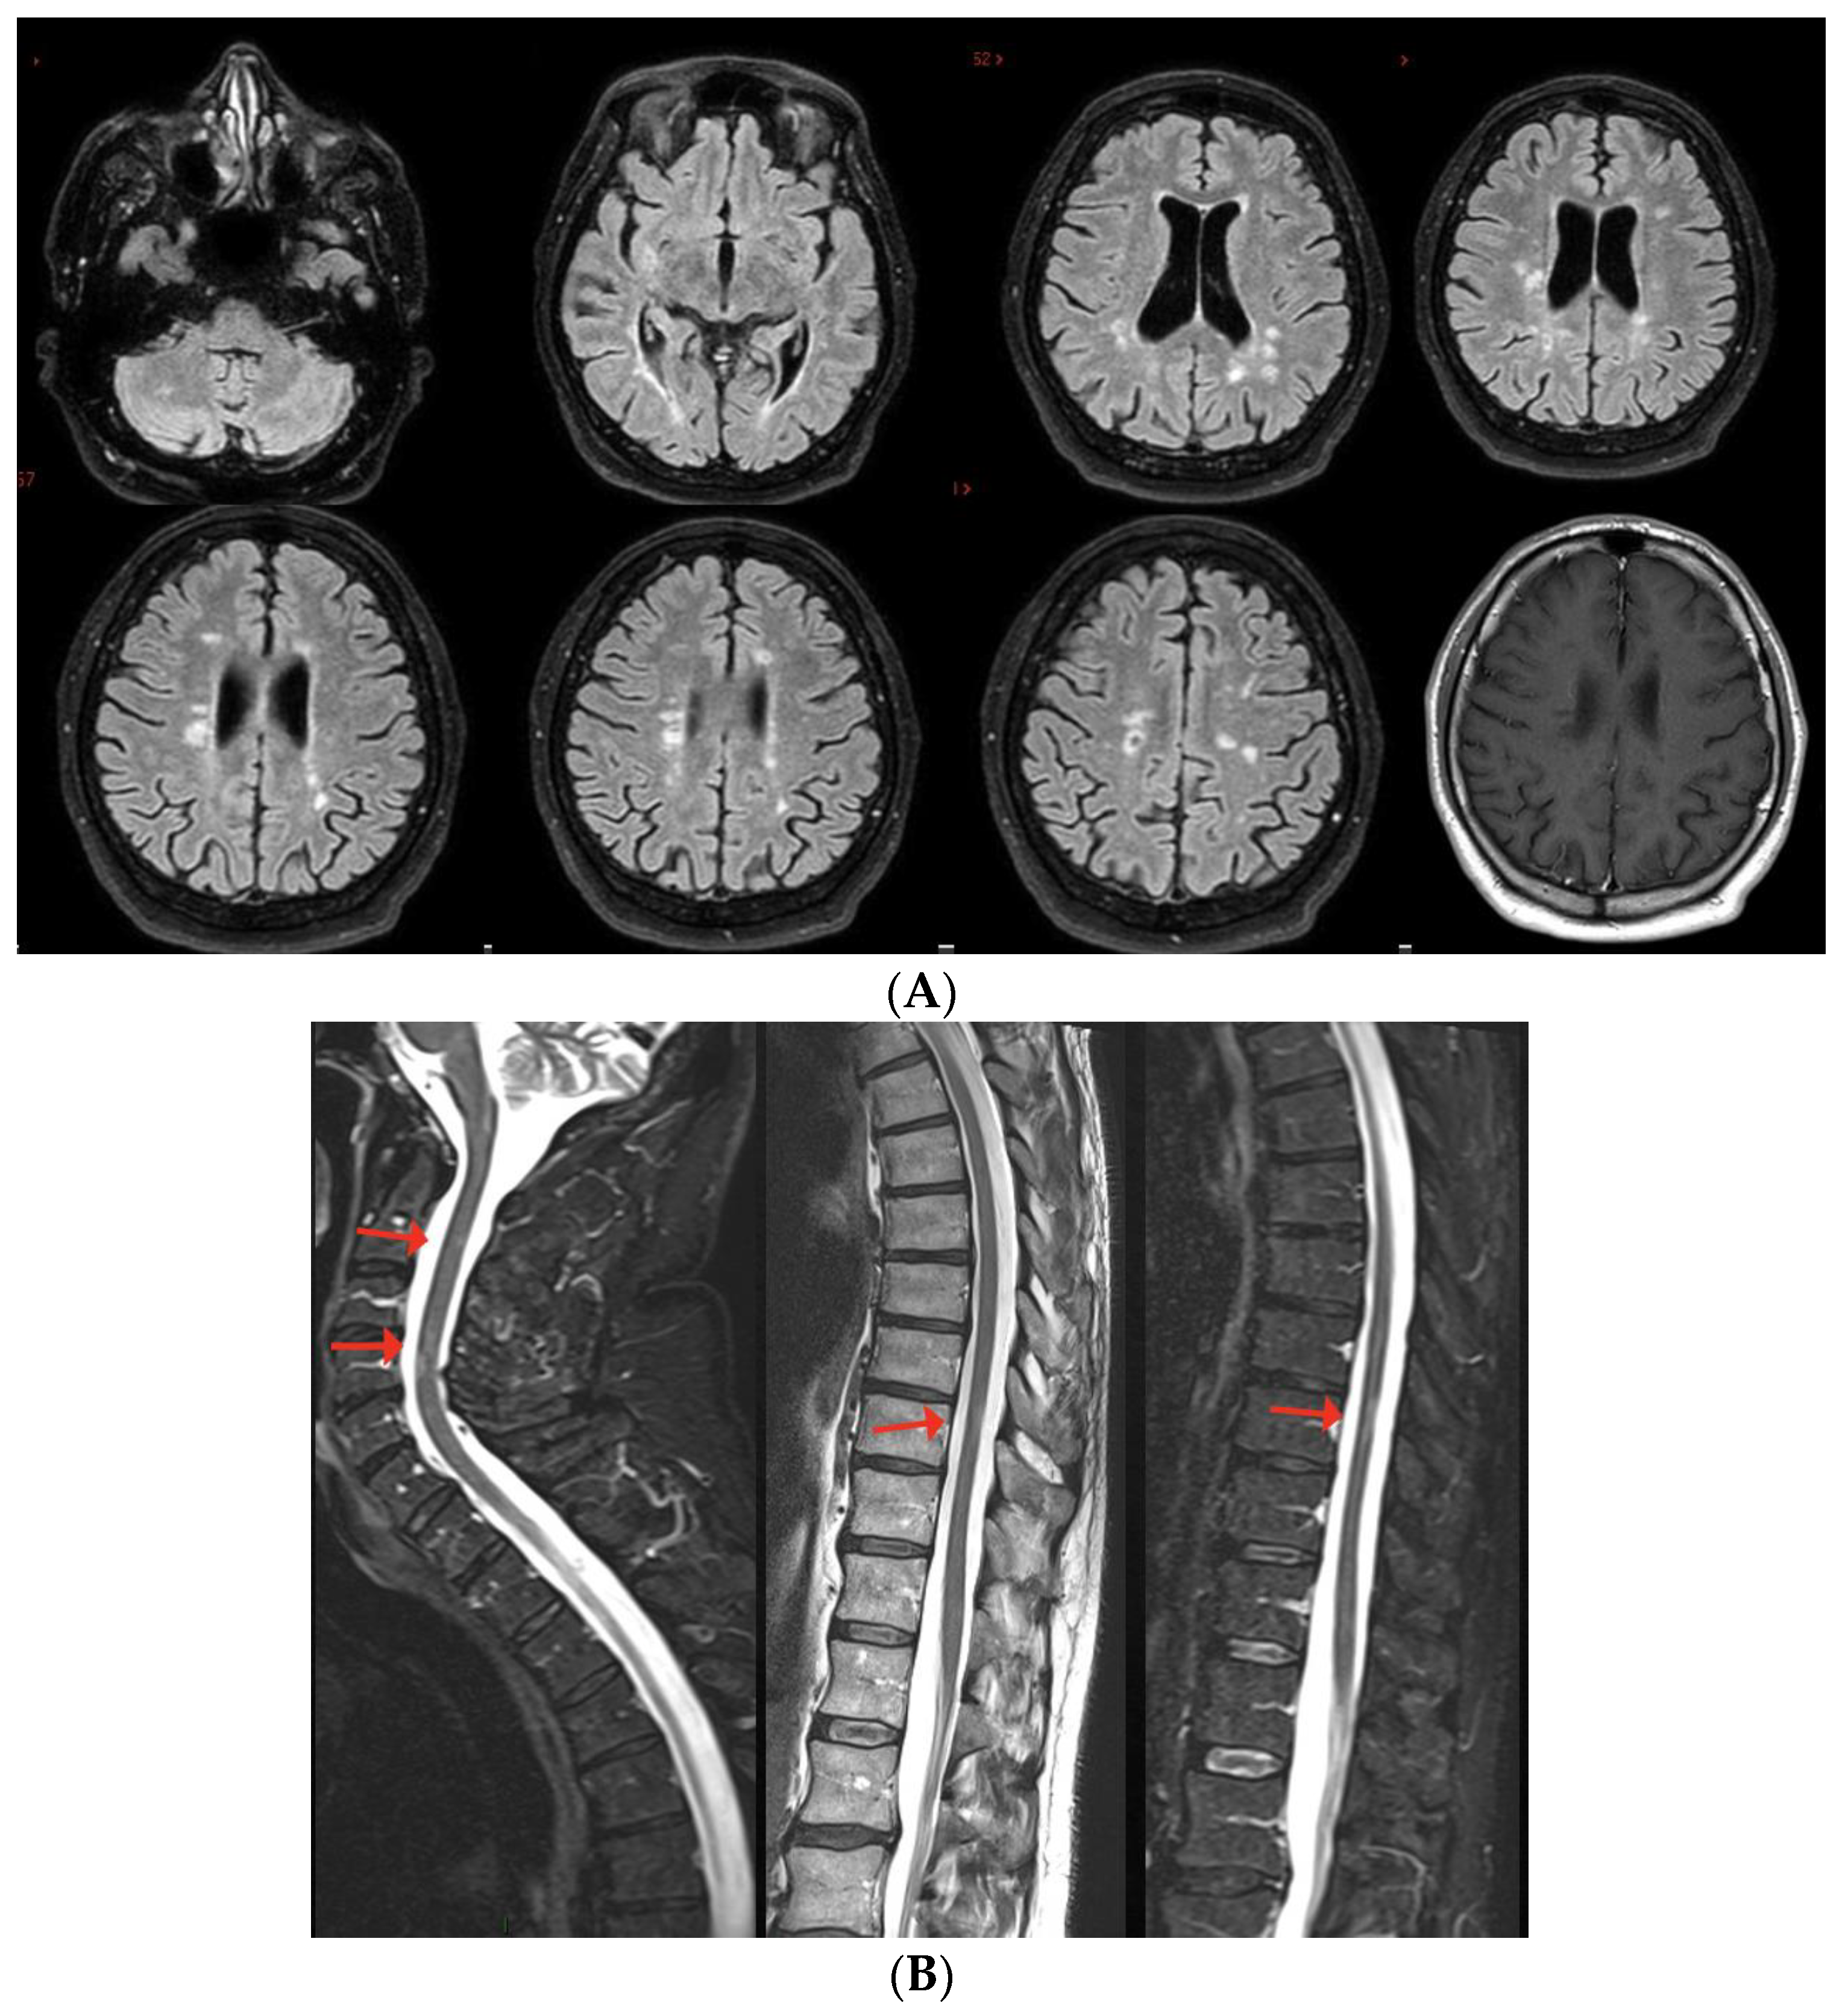

2. MS Onset after SARS-CoV-2 Exposure